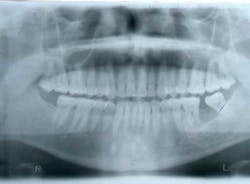

This patient presented with a missing No. 18 and hopeless No. 17 and No. 19 due to localized severe periodontal disease, recurring abscesses, and tooth migration. Severe bone loss can be seen on the initial periapical (Fig. 1) and panoramic (Fig. 2) radiographs.

Fig. 2